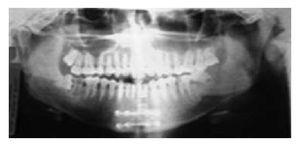

El paciente presenta tumor en el cuerpo mandibular (Imagen 3 se realizó hemimandibulectomía del lado izquierdo, con reconstrucción inmediata a través de la colocación de un implante de la rama mandibular afectada, la fijación se realizó con placa de titanio (Imágenes 4 y 5).

Imagen 3. Ortopantomografía. Imagen radiográfica donde se muestra el grado de extensión de la lesión en el cuerpo de la mandíbula.